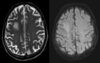

Imaging findings in developmental delay

CNS malformations, white matter abnormalities, cerebral atrophy